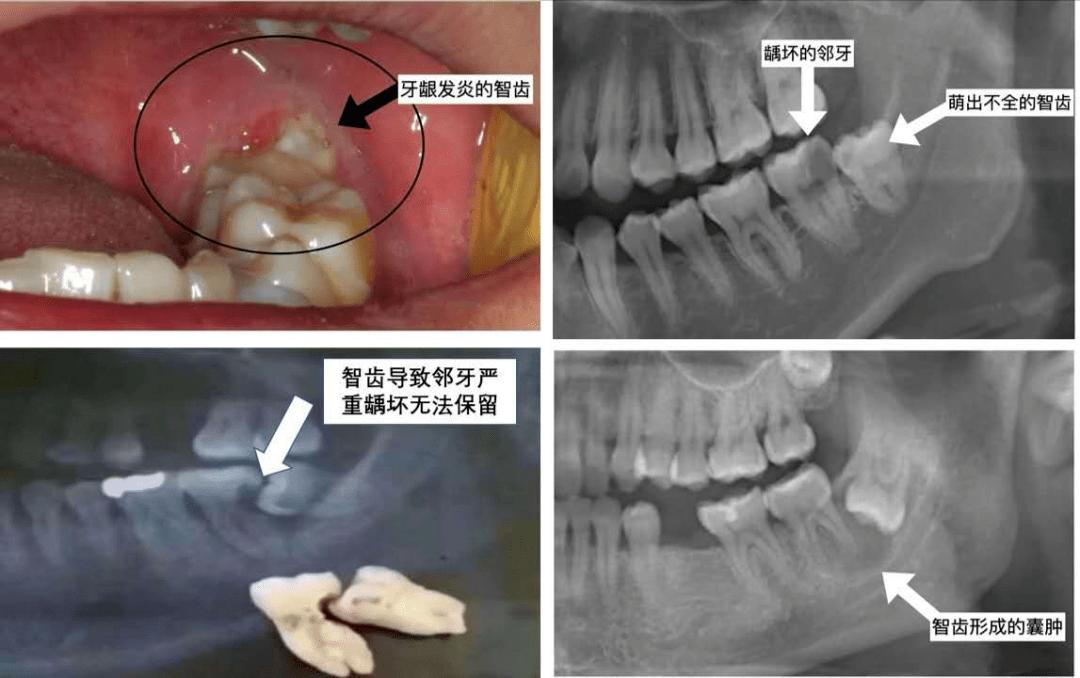

智齿为了长出来,只能“自私”地顶坏前面的牙齿,这也是智齿会引起牙疼、牙龈发炎等问题的原因。

(智齿引起牙疼、牙龈发炎等问题)

尤其是那些“蠢蠢欲动”的智齿,已经引起了牙疼、牙龈发炎等情况,哪怕吃点消炎药将炎症又下去了,后面也会反复发作,并且一次比一次疼,一次比一次严重。